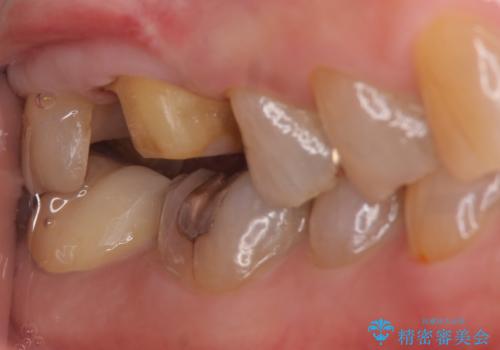

右上6,7の金歯を外したところ、虫歯が歯茎より深い位置まで進行していたため歯周外科を行いました。

その後歯茎の回復を待ち、オールセラミッククラウンおよびセラミックインレーによる補綴・修復を行いました。

虫歯が進み歯茎より深くなってしまうと、虫歯を取り残してしまうリスク、樹脂の硬化の妨げ、補綴物の不適合、歯肉炎・歯周病のリスクの増大等様々な弊害が起こり得ます。

そのため当院では歯周外科手術(歯茎を下げる手術)や歯の挺出による、虫歯が歯茎より深いという問題の解決を推奨しております。